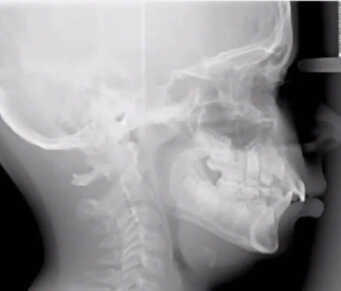

Sleep Apnea In Children Example

While obstructive sleep apnea is commonly associated with adults, it is important to recognize that children can also be affected by this condition. Pediatric obstructive sleep apnea refers to a sleep disorder in which a child’s breathing is partially or completely obstructed during sleep, leading to disrupted breathing patterns and inadequate rest. The underlying cause of this condition is often the narrowing or blockage of the upper airway during sleep.

Enlarged tonsils or adenoids are frequent culprits of obstructive sleep apnea in children. However, other factors, such as genetic predisposition, nasal allergies, Down syndrome or cerebral palsy, may also increase the risk of pediatric sleep apnea.